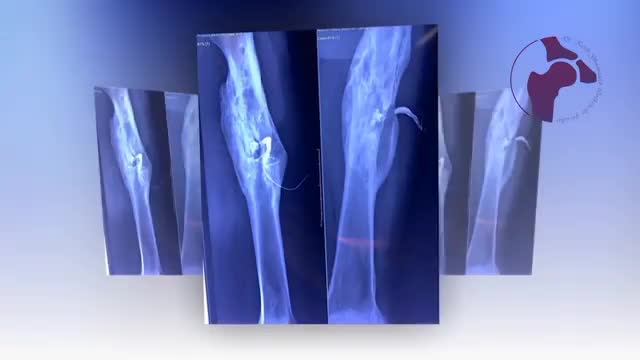

عفونت مزمن استخوان